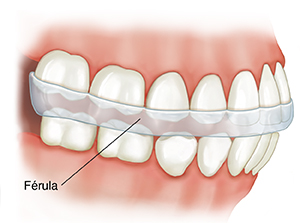

El bruxismo (rechinamiento de dientes) o el apretamiento excesivo de los dientes fuerzan demasiado la articulación temporomandibular y los músculos relacionados. Si tiene estos hábitos durante el día, una autorrevisión puede ayudarlo a dejarlos. Pero es difícil controlar estos hábitos mientras duerme. En este caso puede resultar útil el uso de una férula.

Cómo funciona una férula. Una férula es un aparato que se pone en la boca. También se lo llama “ortesis” o “protector bucal”. Existen diversos tipos de férulas para distintos casos. La férula sirve para mantener la separación entre los dientes superiores y los inferiores. Ayuda a proteger las superficies dentales contra el rechinamiento. También puede servir para reducir el esfuerzo en la zona afectada.

Uso y mantenimiento de la férula. Antes de hacer la férula, el dentista o el ortodoncista tomará una impresión de sus dientes. Luego hará un aparato que le encaje bien en la boca. La férula:

Puede usarse durante el día o bien solo durante la noche. Pregunte cuándo y con qué frecuencia debe ponerse la férula.

Debe limpiarse antes de ponerla en la boca y después de sacarla. Pregunte a su dentista u ortodoncista cómo limpiarla.

Debe guardarse en un estuche protector, fuera del alcance de los niños y de las mascotas. Esto ayuda a evitar que se ensucie o se rompa.